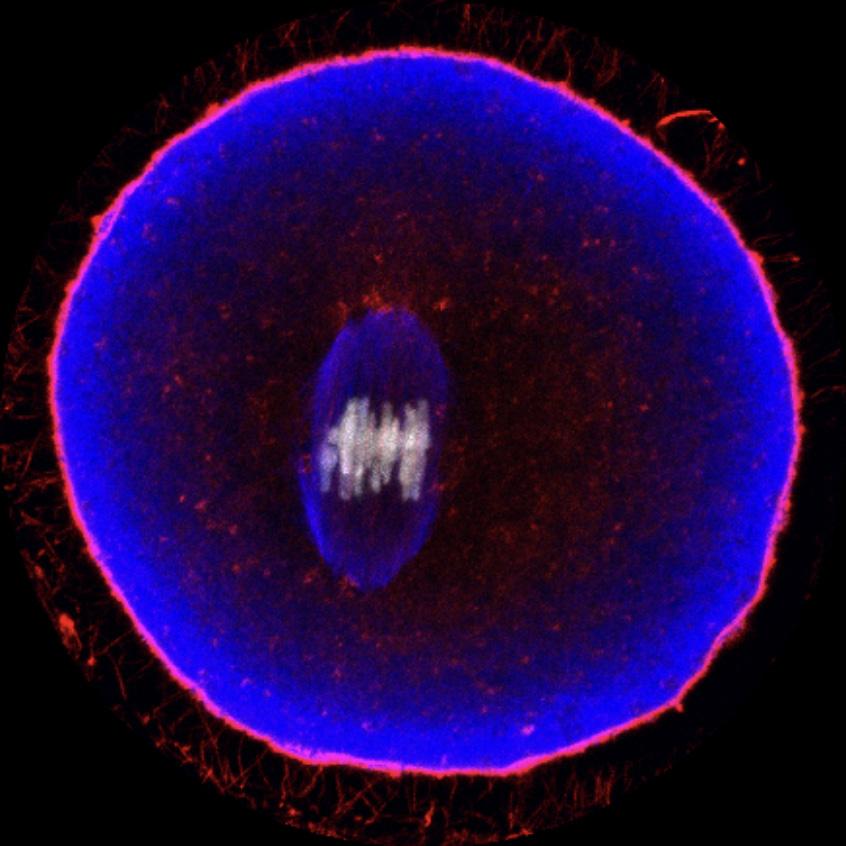

Amongst the most reliable devices is the Ava Fertility Tracker (top photo). It is a bracelet worn during sleep which monitors multiple physiological signals to predict ovulation and to identify the fertile window, and was in 2021 the first to receive FDA 510(k) clearance, thereby becoming the first machine learning device approved to aid women in ovulation prediction. This was also followed that same year by the Ava bracelet, the popular Oura ring integrated with the Natural Cycle app (middle photo), also FDAapproved. Although the Oura ring is not in itself cleared by the FDA for fertility tracking, its integration with the approved birth control app Natural Cycles allows for enhanced fertility tracking capabilities. In fact, multiple commercial integrations of wearable devices have been recently launched with the aim of increasing the accuracy of fertility tracking, among those the Kegg plus Mira device (bottom photo), another popular example that combines data from cervical mucus impedance and urine hormone levels.